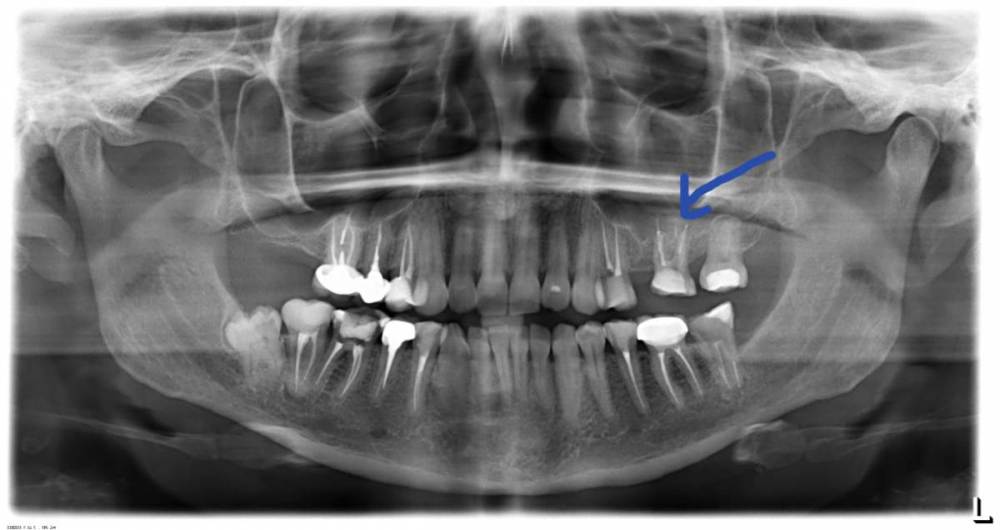

Наталья П. Опубликовано 14 мая, 2021 Поделиться Опубликовано 14 мая, 2021 Здравствуйте! Подскажите пожалуйста что можно сделать? В начале апреля появился свищ, на уже запломбированном зубе без нервов, пломба стояла долго, не тревожила. Доктор почистил каналы и санировал в середине апреля, поставил временную пломбу, и через две недели на осмотре решено было ставить коронку. После снятия слепков (30 апреля), вечером опять образовалась шишечка на десне но к утру прошла. Было решено понаблюдать. На текущий момент зуб ноет не сильно, болит при нажатии, при физических нагрузках чувствую пульсацию. Снимок сделан 14 мая. Что это может быть? Что можно сделать? Буду очень благодарна за ответ. Ссылка на комментарий

St. Опубликовано 14 мая, 2021 Поделиться Опубликовано 14 мая, 2021 Есть ли еще какие-то снимки этого зуба до и после лечения каналов? Можно пока восстановить зуб временной пластмассовой коронкой приклееной на прочный материал на 6 мес. и посмотреть динамику а запротезировать постоянной коронкой позже. Ссылка на комментарий